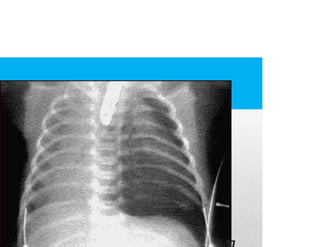

CONTUSION

PULMONAR

• Pulmon se lacera o rompe por mecanismo romo

o penetrante.

• No entra aire en los alveolos.

• Es una complicacion frecuente.